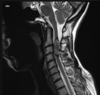

Deficiência de b12 ou cobre; Ocorre o Acometimento dos funículos posteriores (grácil e cuneiforme) e porção posterior dos funículos laterais (tratos cortico-espinhais laterais) *por isso combinada; Lesão de hipersinal T2 na porção posterior da medula, com sinal do V invertido no corte axial; acomete mais comumente medula cervical e torácica.